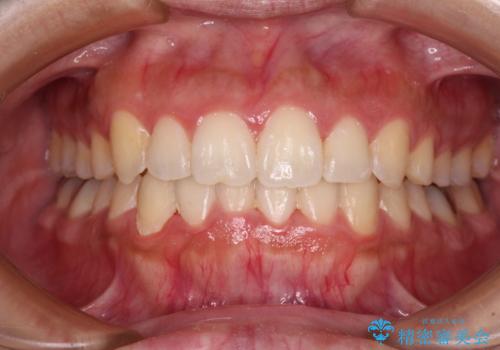

[インビザライン] 前歯のガタつき・すれ違い マウスピース矯正治療